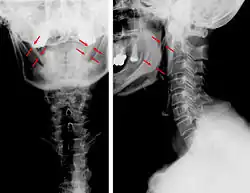

| Anteroposterior and lateral radiographs of cervical spine showing ossification of the stylohyoid ligament on both sides | |

Radiograph, lateral view showing elongated stylohyoid process and stylohyoid ligament ossification -

Radiograph, lateral view showing joint-like formation in ossified stylohyoid ligament -

Imaging is important and is diagnostic. Visualizing the styloid process on a CT scan with 3D reconstruction is the suggested imaging technique.[13] The enlarged styloid may be visible on an orthopantogram or a lateral soft tissue X ray of the neck.